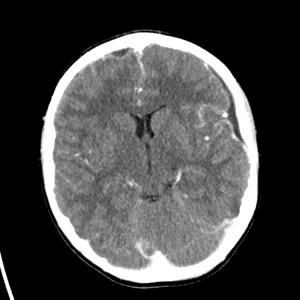

Watershed ischemia

Cardioembolic infarcts

Deep venous infarct